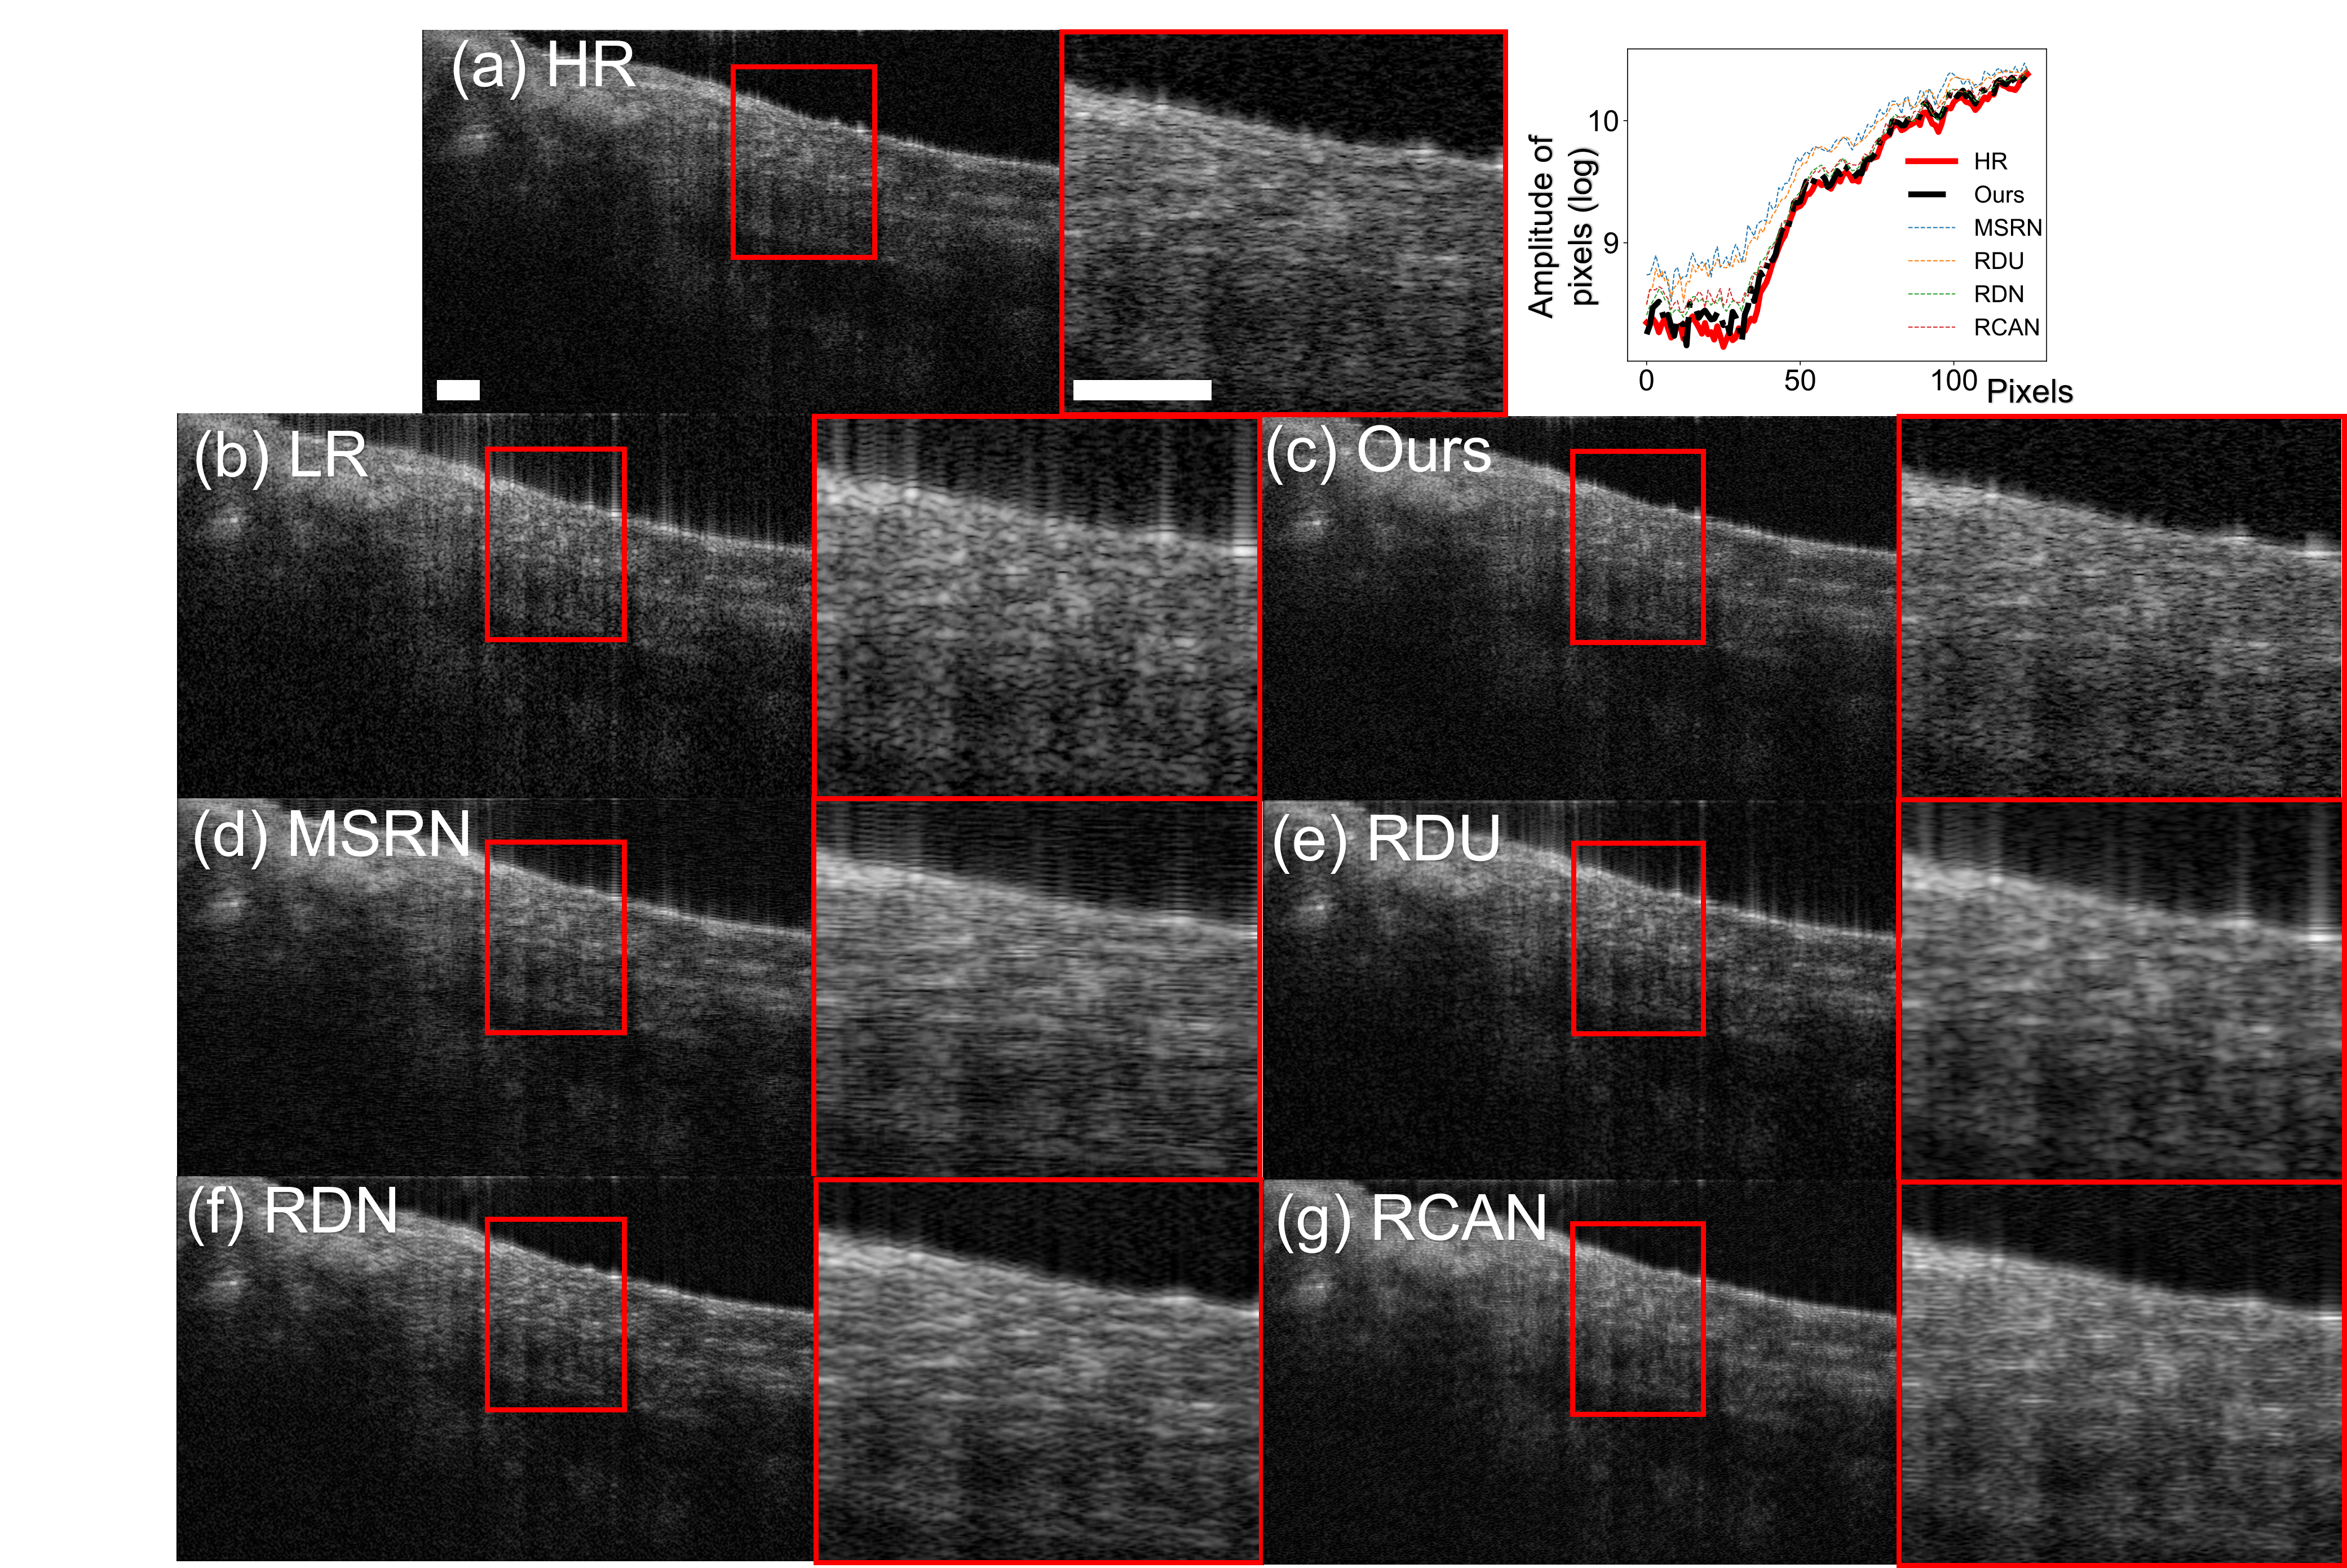

However, the current DL research in generating SR OCT images focuses solely on the spatial distribution of pixels in B-scans, without consideration of frequency information. The lack of frequency-awareness poses limitation on SR performance in two aspects. Firstly, from 1-D frequency perspective, SDOCT is physically measured in spectrum and reconstructed in spatial domain. Considering frequency information along axial direction would increase the fidelity of reconstruction. Secondly, from 2-D image processing perspective, current DL models exhibit spectral bias, which is a learning bias towards low-frequency components [26, 27]. As shown in Fig 1, DL algorithms induce frequency domain gaps in SR OCT images compared to the reference HR images, as they fail to resemble the high-frequency components, such as edges and textures of the coronary artery sample. High-frequency components preserve finer details that are beneficial for medical imaging [28]. Therefore, a DL framework with frequency awareness is needed to reduce spectral bias and generate high-quality SR OCT images.

3.6 Analysis on spectral bias

We perform frequency analysis to evaluate the spectral bias of our frequency-aware model and other DL algorithms. We apply 2D DFT to the HR and SR OCT images, after which we average the logarithm of the intensities for each A-line and plot the intensity values over the pixels. The frequency analysis is carried out by averaging the spectrum of the SR OCT images. The results are reported in Fig 3. As shown in Fig 3 (a), our frequency-aware model generates SR images with averaged spectrums that are similar to the HR images. The summed intensities for pixels, as shown in Fig 3 (b), confirm our frequency-aware model are less biased in spectrum distribution compared with other DL algorithms. On the other hand, existing DL algorithms generate SR OCT images with spectral bias in an unstable manner, as confirmed by Fig 3.

3.7 Quantitative analysis on super-resolution performance

We compare the quantitative performance of our frequency-aware model to other DL algorithms. As shown in Table 1, our frequency-aware model generates SR OCT images with better PSNR, SSIM, and SFD scores compared to other deep learning algorithms. Together with Fig 3, we confirm our frequency-aware model generates SR OCT images with better spatial and frequency properties compared to other DL algorithms.

In Fig 4, a case of super-resolving an LR OCT image of a stent within the coronary artery is demonstrated. Coronary stent placement is an established treatment for CAD [33]. Imaging microstructures and tissues adjacent to stent struts are crucial in the clinic. It is critical to provide accurate morphological information on interactions between the stent and the vessel wall, for the purpose of evaluating the placement as well as the biocompatibility of the stent. The edges of the stent are considered to be high-frequency information in the OCT images, which are challenging to reconstruct for previous DL algorithms. As shown in Fig 4, previous DL algorithms generate blurred edges of the stent. Moreover, existing DL algorithms lead to artifacts on the interaction between the stent and tissue, as shown in Fig 4 (e), (f), (g). With our frequency-aware model, the edges of the stent are resolved with detailed information that is similar to that of the HR image.